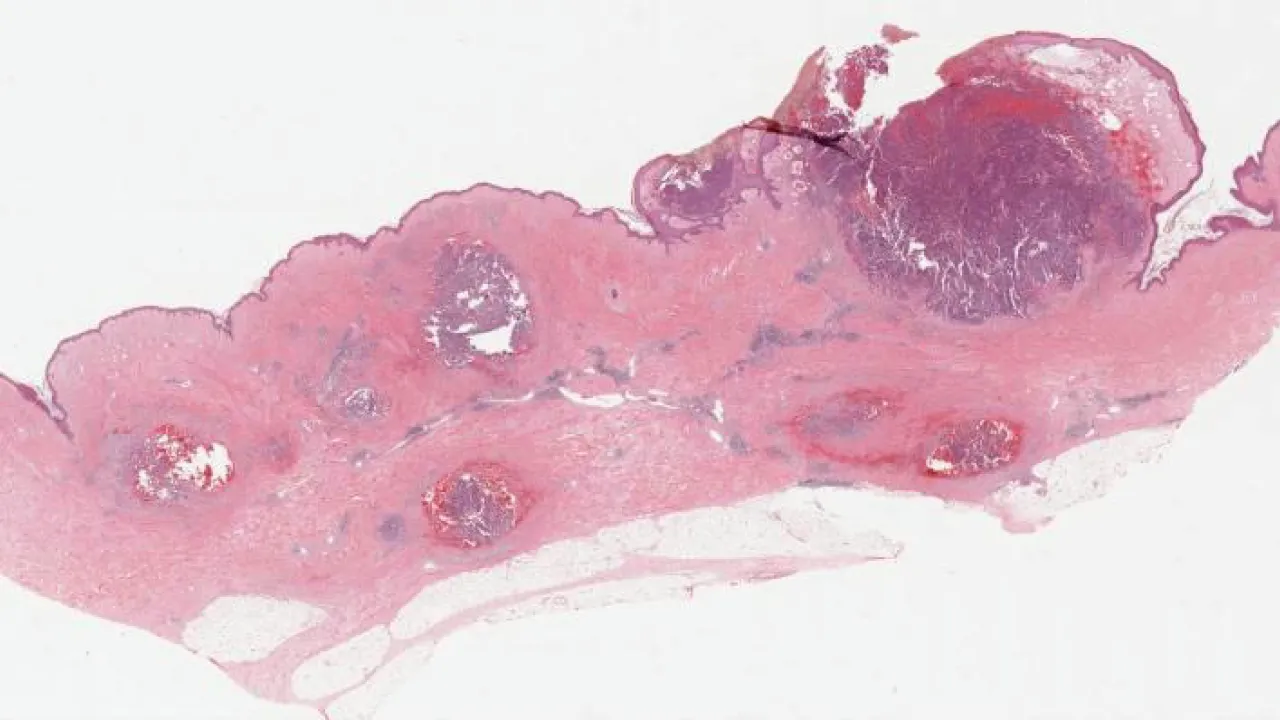

Skin, Pyogenic granuloma

Skin, Seborrheic keratosis

Skin, Seborrheic keratosis, clonal subtype

Skin, Venous lake

Skin, Sebaceous adenoma

Skin, Sebaceous nevus

Skin, Malignant Melanoma